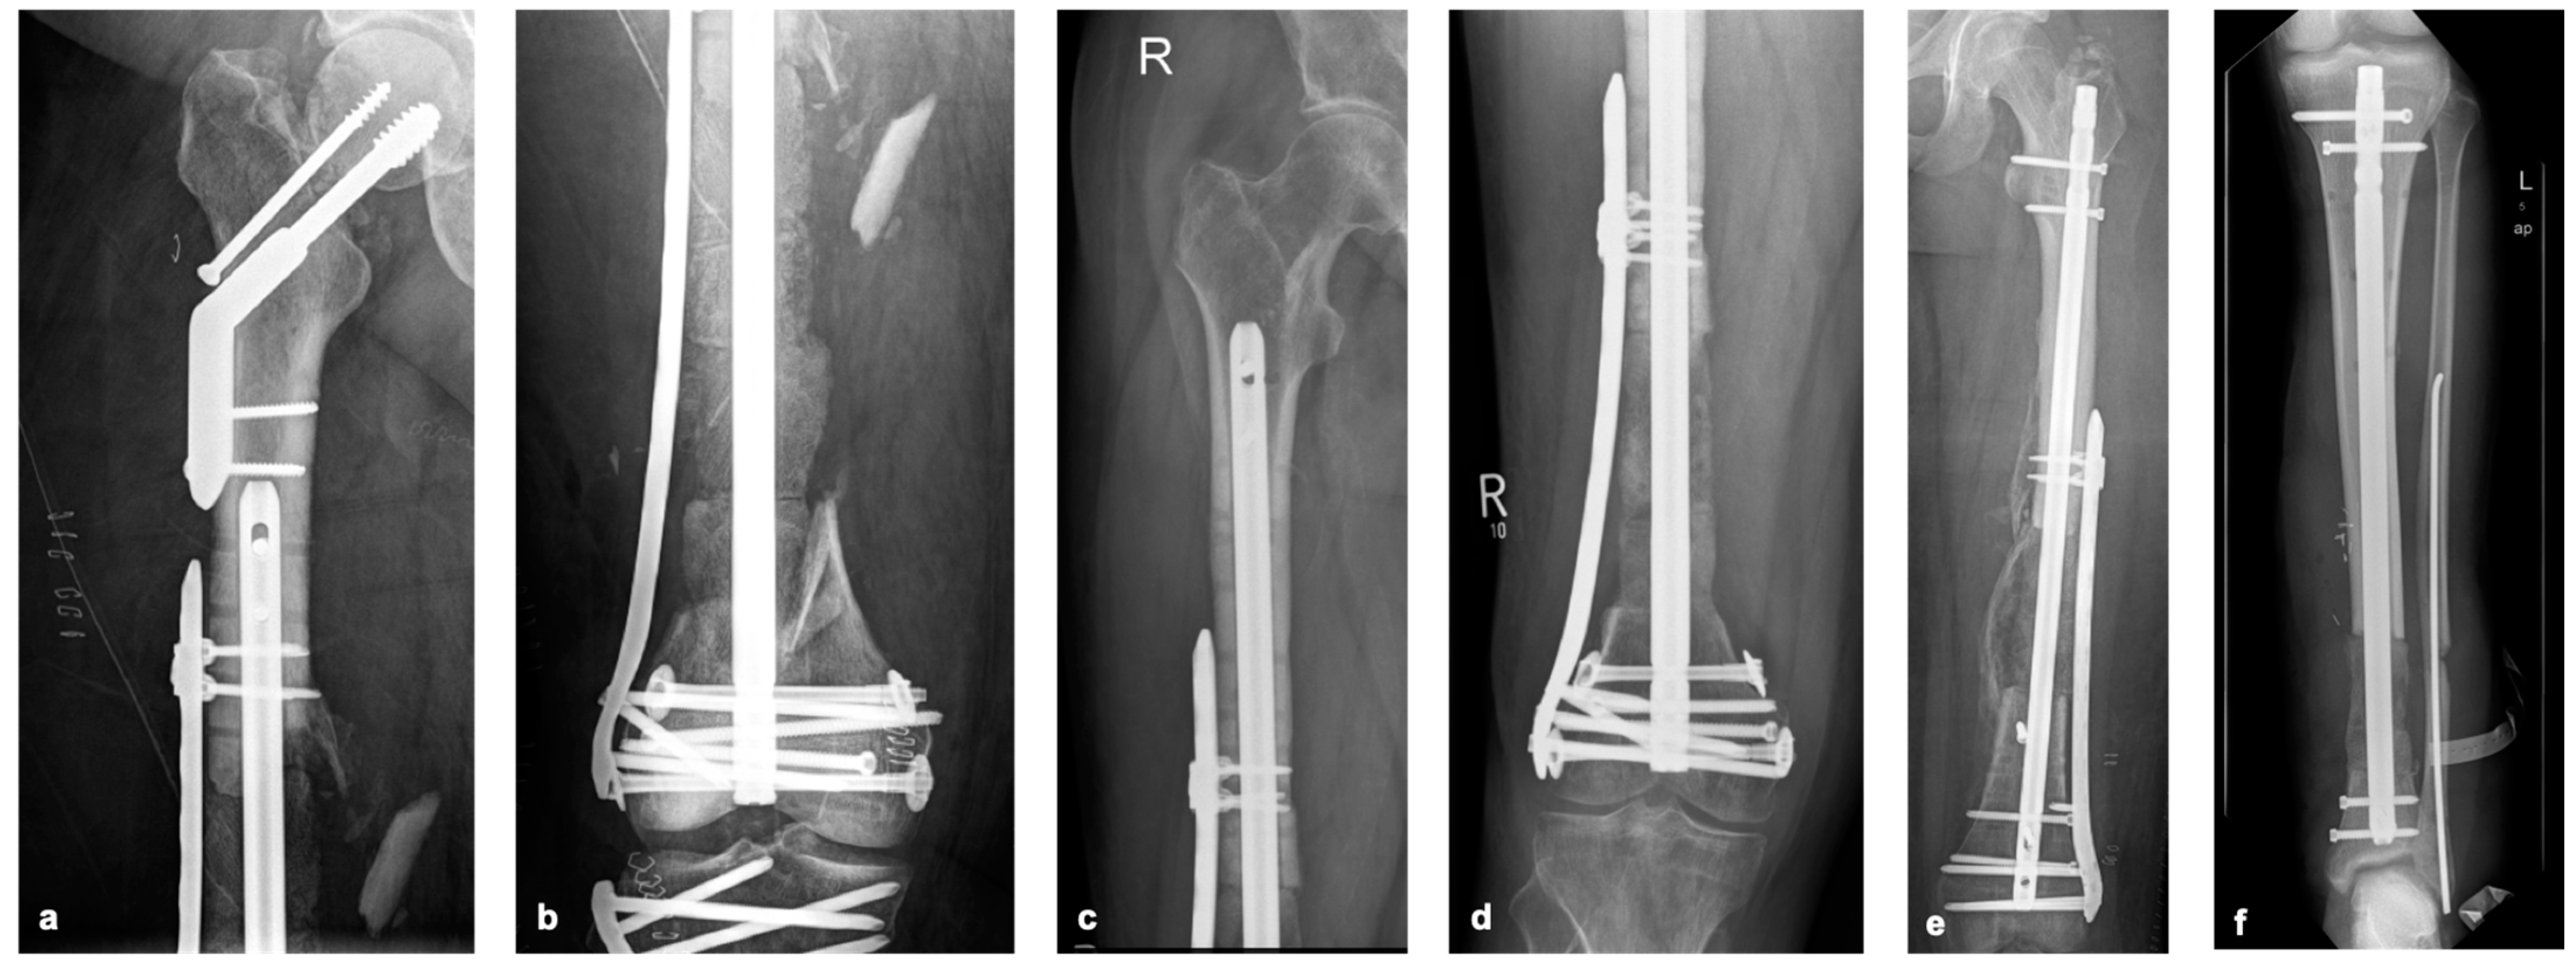

Based on our experience, the absolute stability of the selected osteosynthesis and bone graft is essential in the reconstruction of (larger) bone defects. If defects are present in the isthmus area of long bones, osteosynthesis with a sufficiently strong nail may be sufficient. If there is insufficient stability, locking plates should be used additionally (Figure 4a,b). In the joint area, additional locking double-plate osteosynthesis is typically preferred in our hands (Figure 5a–f).

Figure 5. Postoperative X-ray after reconstruction of bone defects of the femur and tibia using the pearl-string technique (PST), case from Figure 4a,b 48 hours after surgery (a,b), other cases (cf) describing the PST in other patients at 3-month follow-up.